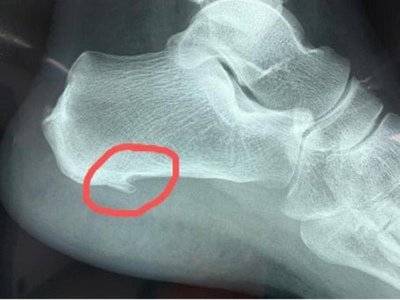

典型x线片

我又看了看这个小男孩的片子单纯看课件和右脚x片,你是不是认为这个小